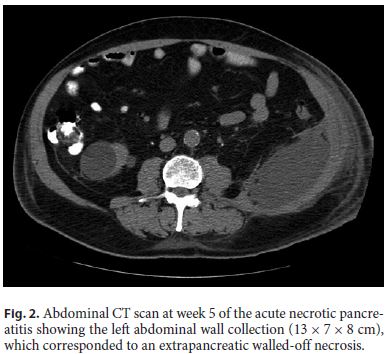

Even though there was a favorable response in the beginning, 10 days later, there was a new fever peak, of 38.6 ° C, and IP rose again (with a maximum CRP of 7 mg/dL). Abdominal CT showed increase in the left abdominal wall collection size (13 × 7 × 8 cm), corresponding to an extrapancreatic WON (Fig. 2).